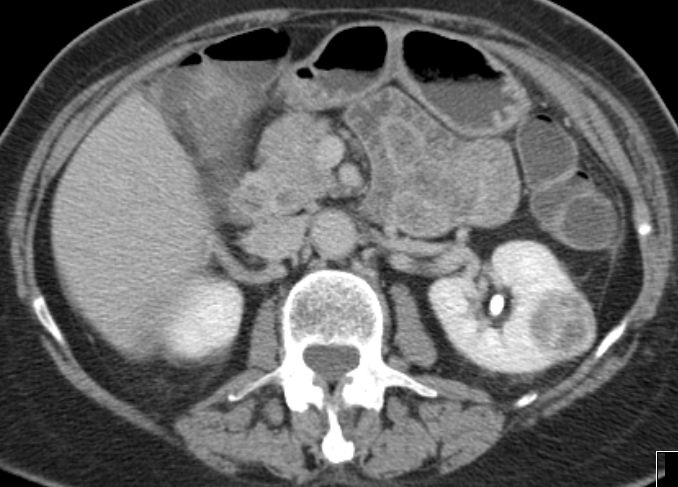

| 14% regionale Lymphknoten, 31% Lunge, 15% Knochen | MRT: Knochenmetastasen

![]() | ||